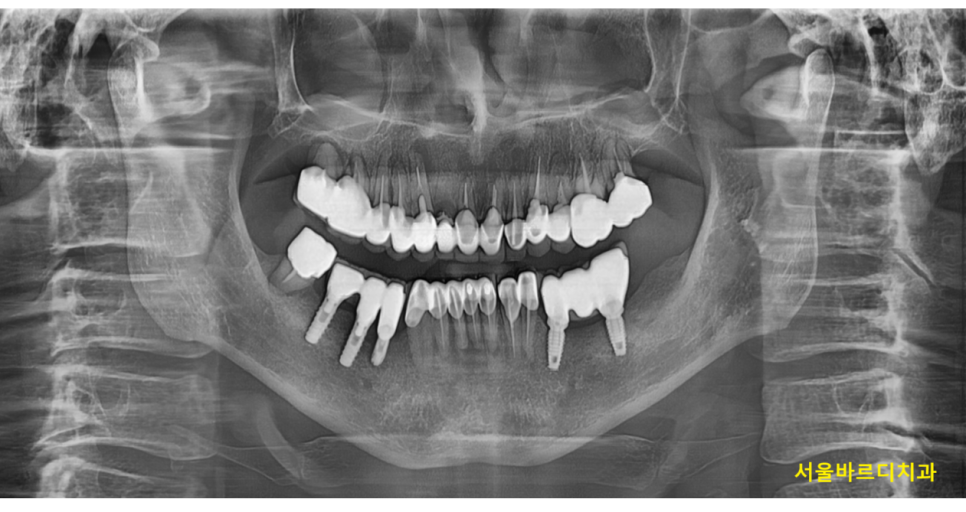

입안에 전체적으로 보철을 한 상태입니다.

치료를 안한 치아는 한개도 없는 상황이죠~

검사를 해보니...

기존 신경치료를 한 치아에 문제가 있어보였는데요.

230607

입에서 냄새가 나는 이유는 많지만

신경치료 한 치아 뿌리 끝 부분으로 뼈가 녹아있고

염증 소견이 확인됩니다.

총 4군데에서 문제가 있었지만

가장 안좋은 부분은 오른쪽 위아래

이 부분들은 흔들리고 있었습니다.